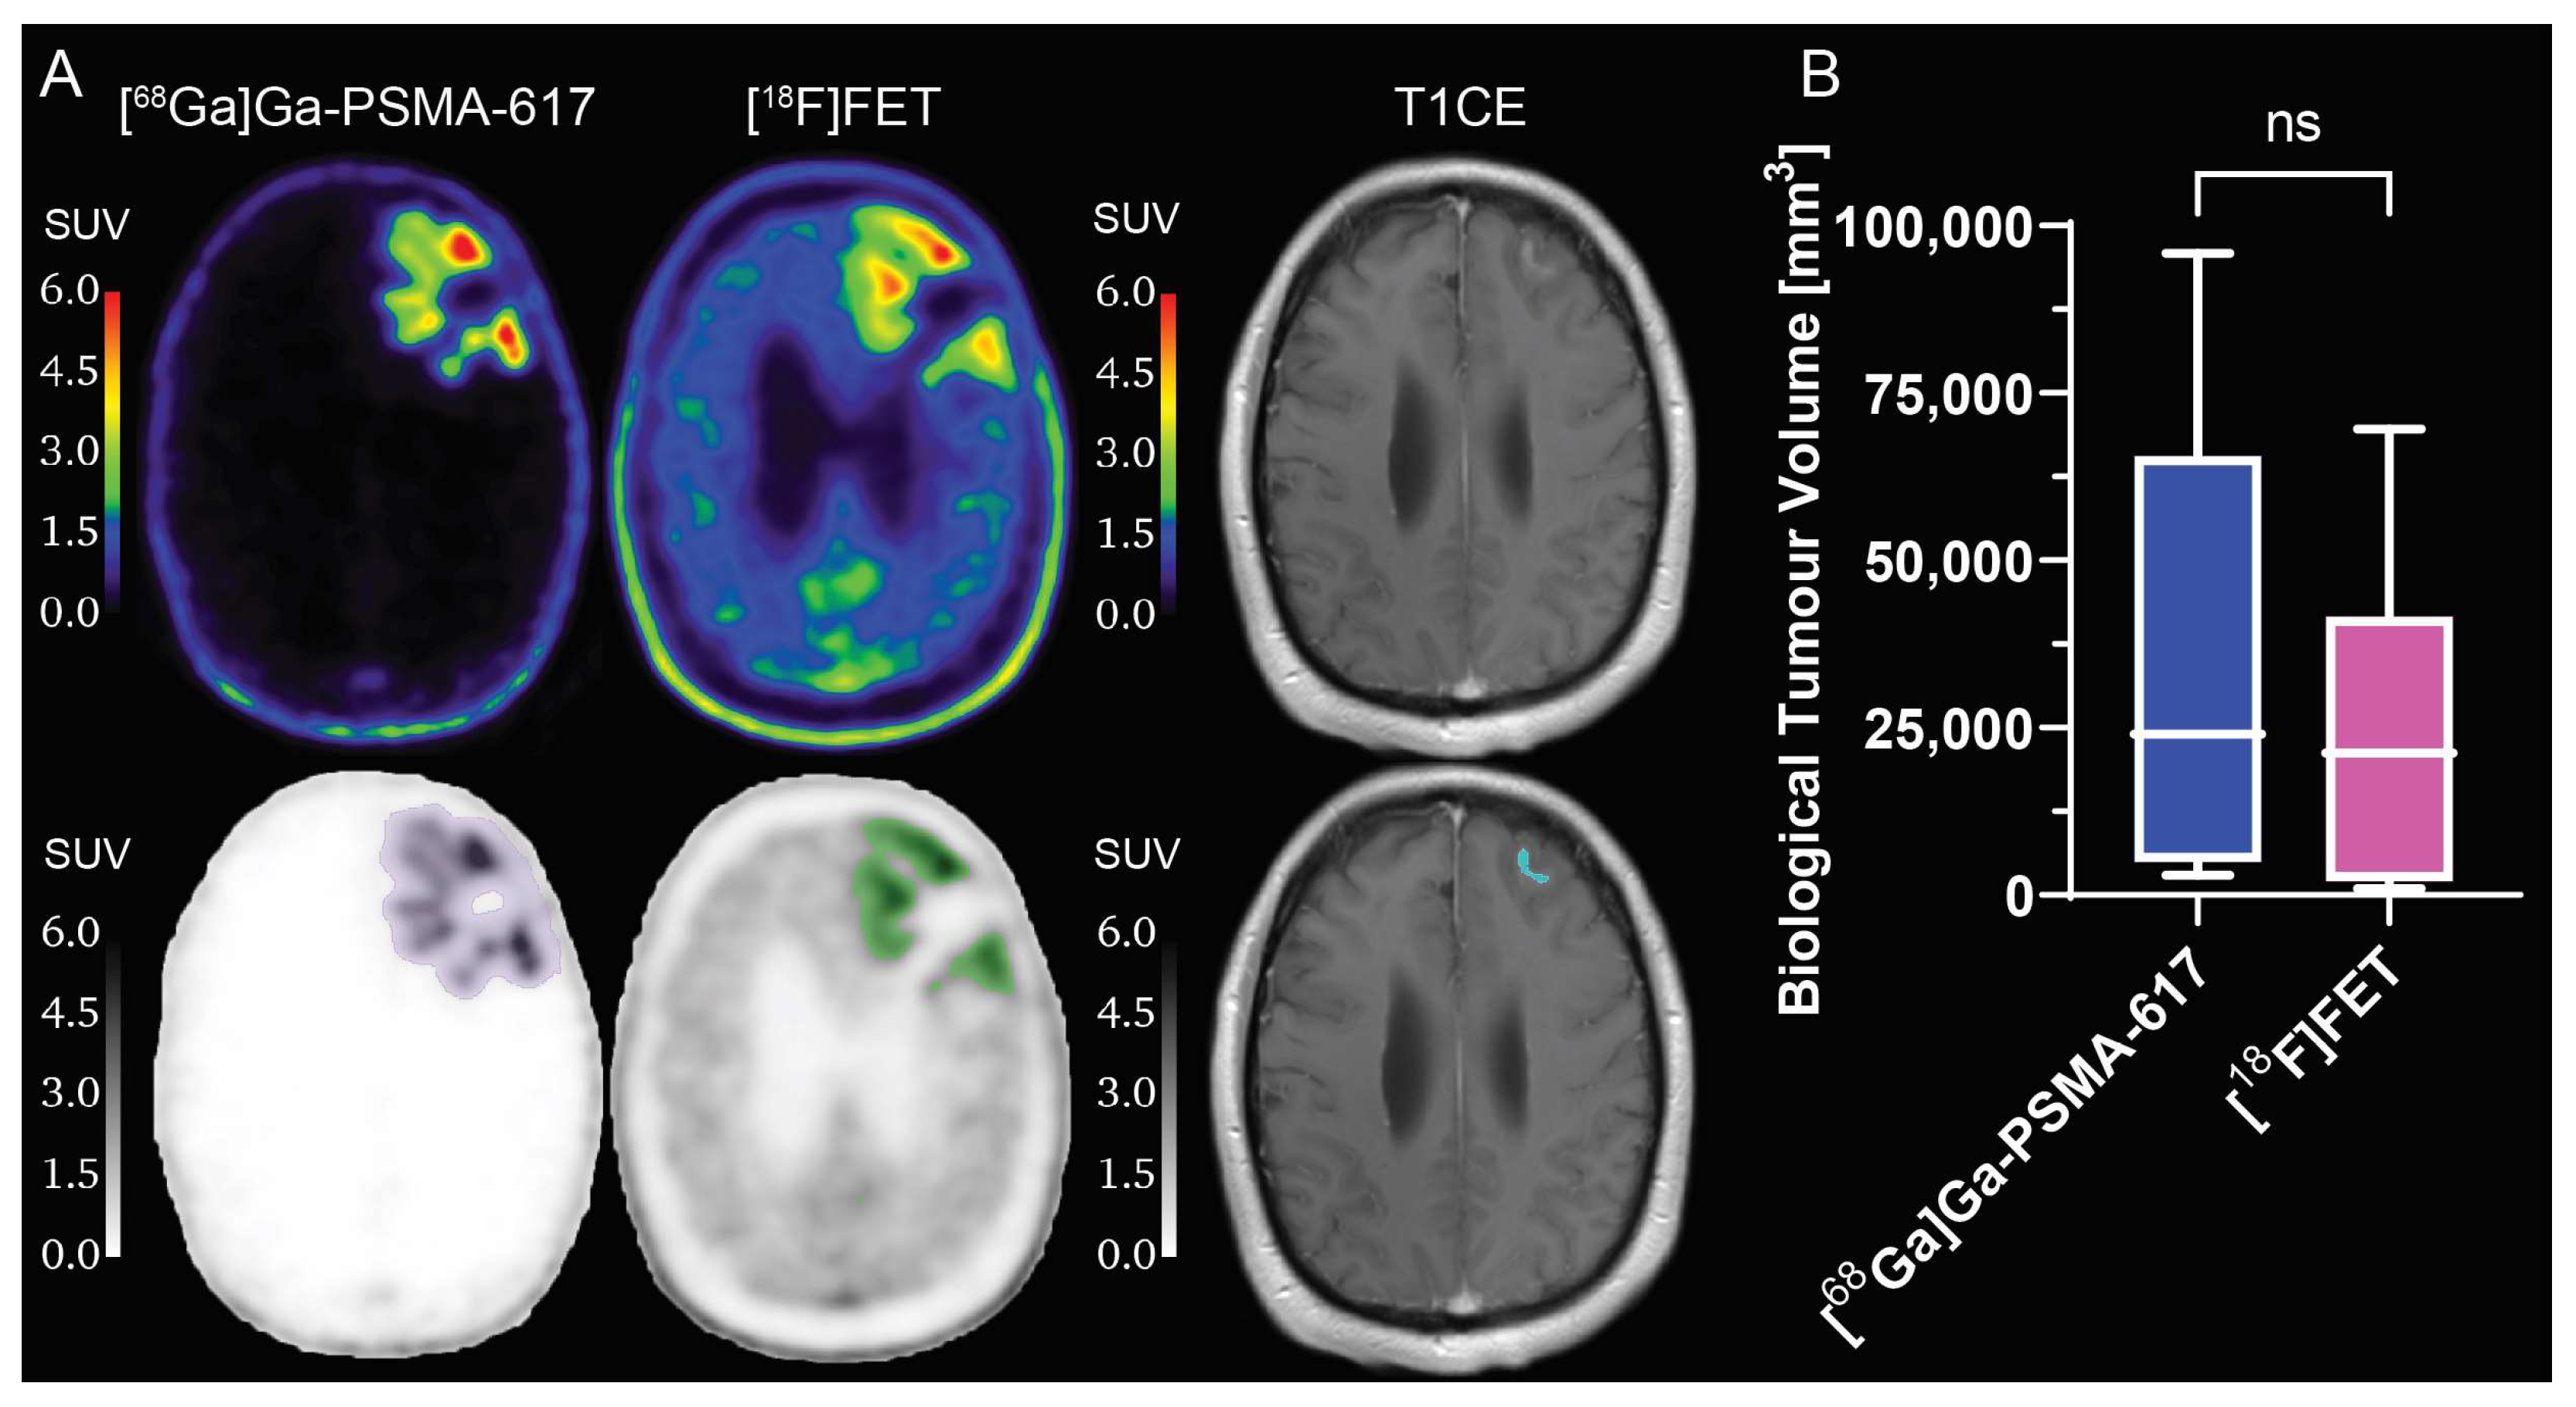

2.3. Comparison between [68Ga]Ga-PSMA-617 and [18F]FET Tumour Specificity